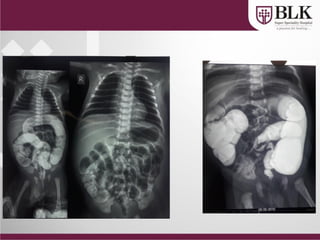

Double Bubble

Triple Bubble

Multiple air fluid level

Ileal Atresia

• Ileal atresia

• NEC

• Total colonic

aganglionosis

• Meconium Ileus

D/D